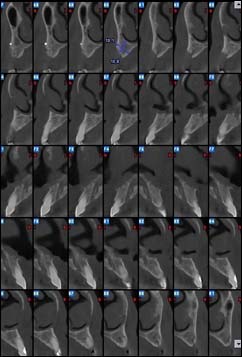

EXAMENS TOMOGRAPHIES VOLUMIQUES TYPE SCANNER OU CÔNE BEAM :

Dernière technologie à notre disposition, cette technique permet de voir en 3 dimensions des images de votre bouche et de mettre en évidence des pathologies ou des anomalies que les autres techniques ne permettent pas d’objectiver.

Reconstruction coronale